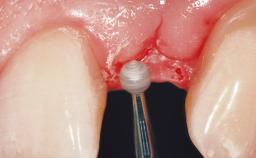

After flapless tooth removal and a healing period of 6 weeks a diameter-reduced two-piece implant is placed. The bone defect on the facial aspect is corrected with a contour augmentation using autologous bone chips covered with DBBM particles and a collagen membrane according to the Guided Bone Regeneration (GBR) approach.